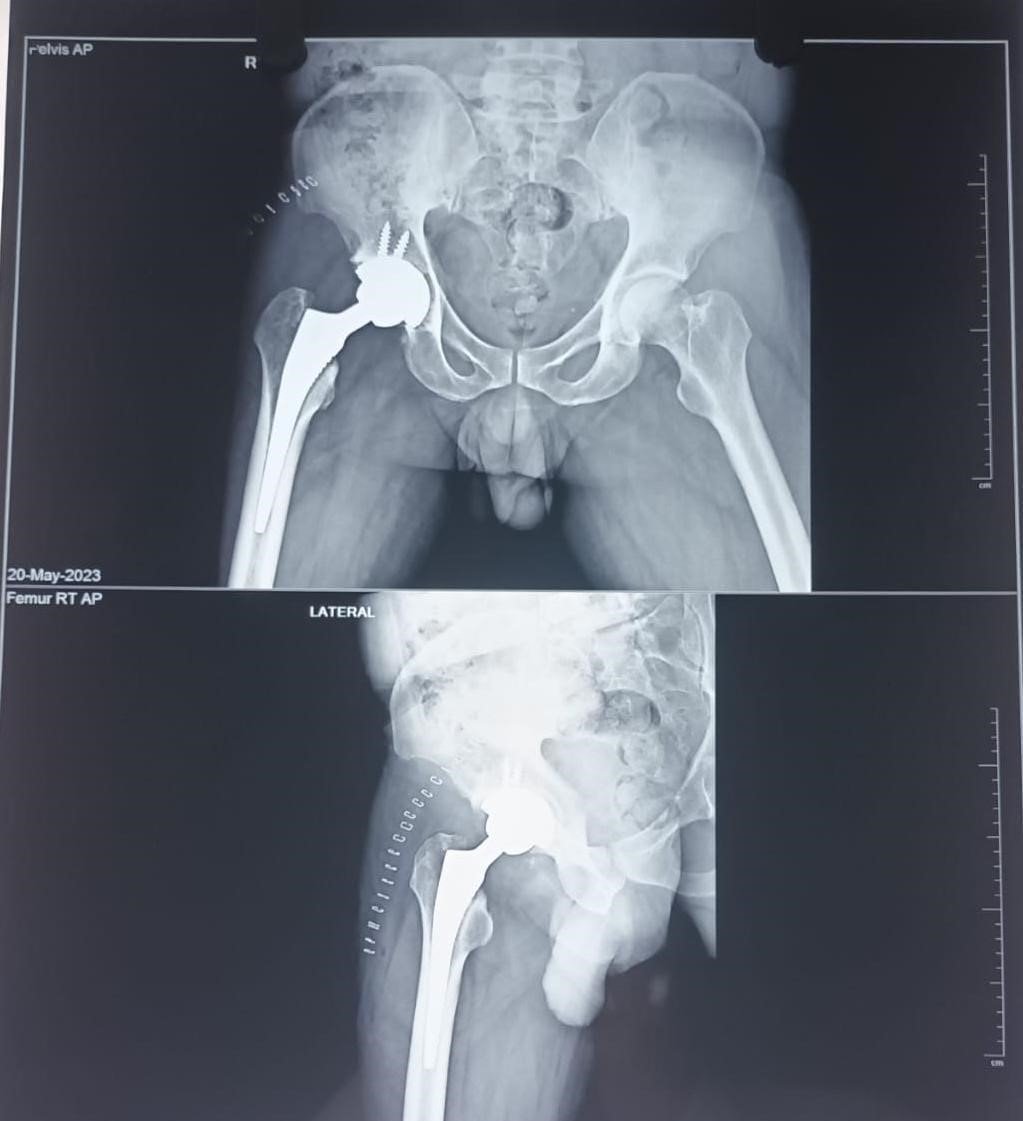

Total Hip Replacement (THR) involves replacing the damaged parts of the hip joint with artificial components called prostheses. The procedure typically includes replacing the damaged ball of the thigh bone (femoral head) and the socket of the hip joint with specially designed implants made of metal, ceramic, or medical-grade plastic. These implants help recreate the smooth movement of a healthy hip joint and significantly reduce pain.

Total Hip Replacement surgery involves removing the damaged bone and cartilage from the hip joint and replacing them with artificial implants that allow smooth and stable joint movement. Modern surgical techniques help ensure better accuracy, reduced pain, and quicker recovery for patients.

After surgery, a structured rehabilitation and physiotherapy program is essential to regain strength, improve flexibility, and restore normal walking ability. Most patients experience significant pain relief and improved mobility within a few weeks of the procedure, allowing them to return to their daily activities with greater comfort.